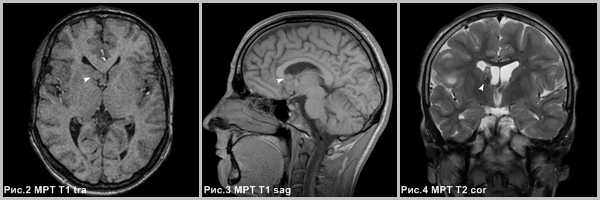

(а) МРТ, Т2-ВИ, аксиальный срез: у юноши с мозжечковой симптоматикой в задней черепной ямке определяется отграниченное гиперинтенсивное на Т2-ВИ объемное образование.

Отсутствие перифокального отека характерно для пилоцитарной астроцитомы. На постконтрастных изображениях определялось контрастирование пристеночного солидного компонента.

(б) МРТ, постконтрастное T1-BИ, аксиальный срез: у ребенка определяется крупное объемное образование, состоящее из кистозного и солидного компонентов.

Обратите внимание на масс-эффект, оказываемый образованием на окружающие структуры. Крупные размеры и гетерогенный характер контрастирования образования могут наводить на мысль о его более высокой степени злокачественности.

При резекции была выявлена пилоцитарная астроцитома (ПА) grade I.

Рис.2,3,4. Субэпендимарная гигантоклеточная астроцитома в области отверстия Монро (головки стрелок на рис.2-4).